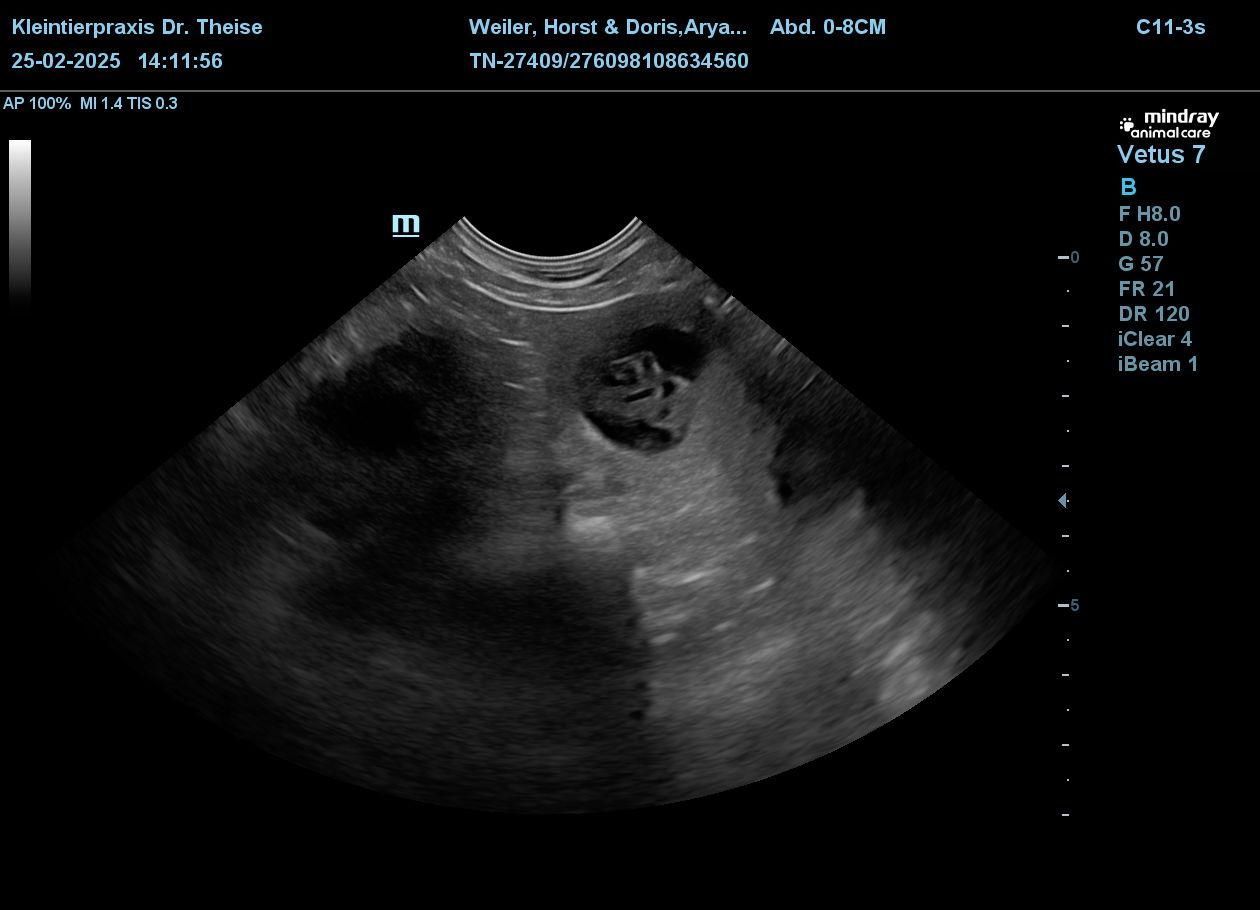

Wir sind so glücklich, Arya ist belegt. Beim Ultraschall wurden 6 Welpen gezählt.